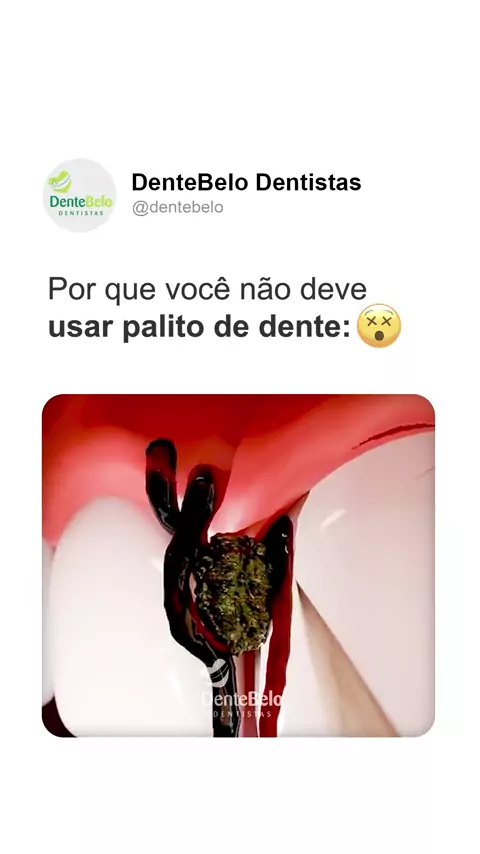

🚫🪥 Parece inofensivo, mas usar palito de dente pode ferir a gengiva, desgastar o esmalte e até empurrar restos de comida para dentro. A escolha certa? Aposte no fio dental para uma limpeza segura e completa. Seu sorriso agradece! 😁✨ 📲 Agende sua avaliação pelo WhatsApp: (51) 3286-2001